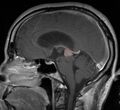

في كثير من الأحيان ، يُعرف شلل الحملقة إالعلوي جنبًا إلى جنب مع العديد من الموجودات العينية مثل رأرأة تراجع التقارب وتراجع الجفن المعروف أيضًا باسم علامة كولير وانفصال الضوء القريب (تتكيف الحدقة مع الضوء ولكنها لا تتفاعل مع الضوء) يسموا كمجموعة بمتلازمة بارينو[1] أو متلازمة الدماغ المتوسط الظهرية ، هي الأعراض الجسدية الوحيدة التي تظهر. يحدث هذا بسبب ضغط مركز الحملقة العمودي في سقف الدماغ المتوسط على مستوى الأكيمة العلوية والعصب القحفي III. يتضمن العمل عادةً التصوير العصبي كما يظهر على اليمين.[citation needed]